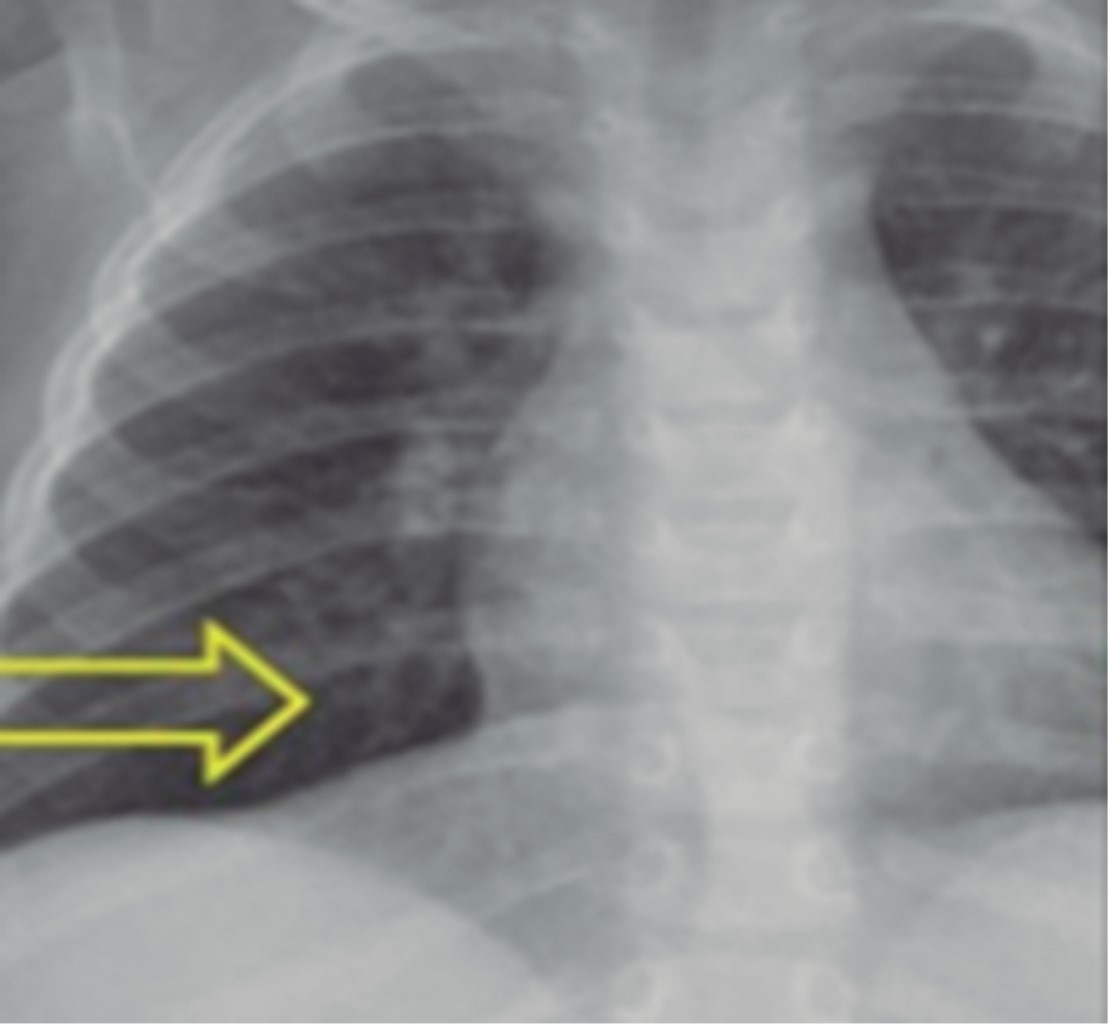

La radiografía de tórax es un estudio de bajo costo que debe realizarse ante la sospecha de aspiración de cuerpo extraño. La radiografía de tórax normal no excluye la presencia de un cuerpo extraño en la vía aérea. Se ha reportado 30-50% de radiografías normales de pacientes con cuerpo extraño alojados en los bronquios.9 Otras series reportan 18% de radiografías normales y 48% con hallazgos inespecíficos como hiperinsuflación o atrapamiento de aire, atelectasia, infiltrados o engrosamiento de la pared bronquial (Figuras 1, 2, 3 y 4).10

De los 43 pacientes sometidos a broncoscopia por sospecha de cuerpo extraño, se encontró cuerpo extraño en 27 niños, de los cuales 19 fueron hombres y ocho mujeres con edades entre nueve meses y 12 años con un promedio de tres años con seis meses. La duración de la retención de cuerpo extraño en vía aérea varió de 30 minutos a tres meses con un promedio de seis días, mediana de 24 horas. Los síntomas iniciales fueron tos en 13 pacientes, disnea en seis, cianosis en cinco, desvanecimiento en uno, sialorrea en uno, y un asintomático; los signos y síntomas a la llegada al hospital fueron disnea en ocho pacientes, sibilancias en siete, tos en cuatro, estridor en cuatro, desvanecimiento en dos, sialorrea en uno y un asintomático. Los alimentos fueron el tipo de cuerpo extraño más común (Figura 6), 41% de los pacientes no tuvieron signos radiológicos, 59% sí los tuvo: hiperinsuflación en cinco, cuerpo extraño radiopaco en cinco, atelectasia en tres, engrosamiento de pared bronquial en tres; el bronquio principal derecho fue el sitio anatómico donde más comúnmente se encontró el cuerpo extraño con 15 pacientes, cinco en bronquio principal izquierdo, cuatro en tráquea, uno en cuerdas vocales, uno en laringe y uno en narina.

La aspiración de cuerpo extraño en vía aérea es una situación que pone en peligro la vida, se ha documentado una mortalidad de 0.21 a 3%, en nuestra experiencia no se han establecido decesos por dicha causa. Las tos, cianosis y disnea son los síntomas más comunes de presentación; los hallazgos radiológicos son variables, se reporta en la literatura hasta 25% de los casos; sin embargo, en nuestra experiencia se encontró en 59.2%, la presencia de cuerpos radiopacos en vía aérea observada en una radiografía es patognomónica, se reporta entre 7 y 10% de los casos: en nuestra experiencia la detectamos en 18.5%; según lo describe la literatura mundial, los productos alimentarios son el tipo de cuerpo extraño que se observa con más frecuencia, y el bronquio principal derecho es el sitio más común de localización.